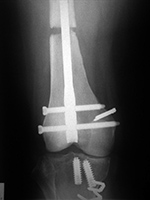

AP and lateral views of the knee show a distal femoral cadevaric limb sparing allograft approximated to the native distal femoral stump by a retrograde intramedullary nail. Two interlocking cannulated screws go through the distal portion of the nail. Cruciate ligament and capsular reattachment were performed with two interference screws and two staples in the proximal tibia and a staple in the posterior aspect of the allograft metaphysis. The patient had a non-specified distal femur sarcoma.